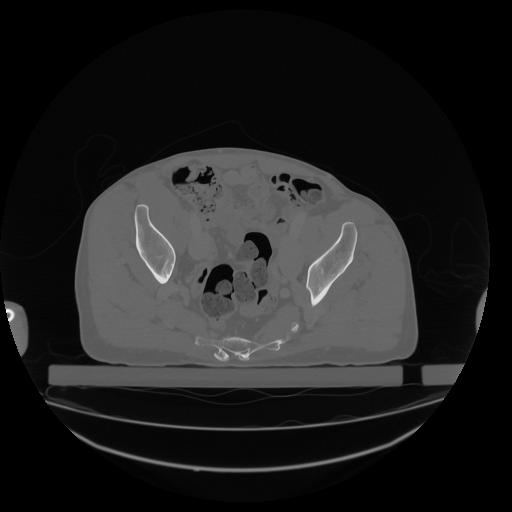

34 CUERPO,CE,Vol,1.0,CUERPO,,